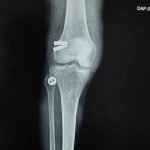

Orthopaedic Surgeon | Arthroscopy & Joint Replacement Specialist

- Robotic Joint Replacement

- Knee Replacement Surgery